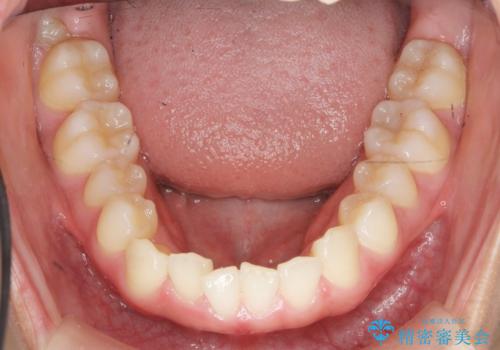

ガタつきの改善 マウスピース矯正治療

- 歯のがたつきの改善を求めて、矯正治療を希望され来院されました。

少量の歯のディスキング、歯列弓拡大、アタッチメントを装着することで審美的な歯列へとマウスピース矯正インビザラインを用いて治療を行います。

マウスピース矯正は装着時間の遵守が非常に大切ですが、しっかりと20時間/日以上の装着を守っていただいたおかげで良好な治療結果を得ることができました。